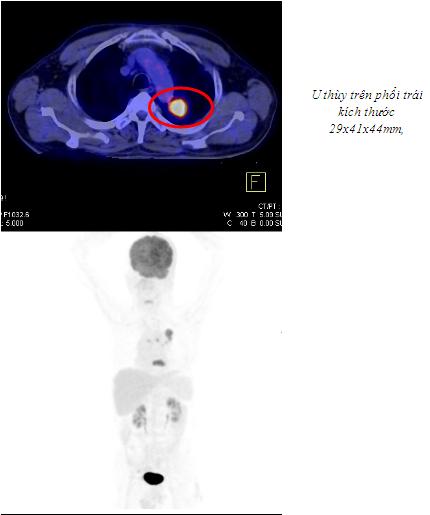

* Bệnh nhân được chụp

PET/CT đánh giá giai đoạn và lập kế hoạch xạ trị giảm đau vào vùng tổn thương

di căn xương:

– U thùy trên phổi trái kích thước 29x41x44mm,

tăng hấp thu FDG, max SUV=9,4.

– Hạch carina kích thước 25x16x20mm, tăng hấp

thu FDG, max SUV=2,0. Hạch dưới quai động mạch chủ kích thước 23x22x25mm, max

SUV=3,5.

– Tổn thương tiêu xương đốt sống D9 xâm lấn phần

mềm, tăng hấp thu FDG, max SUV=9,9.